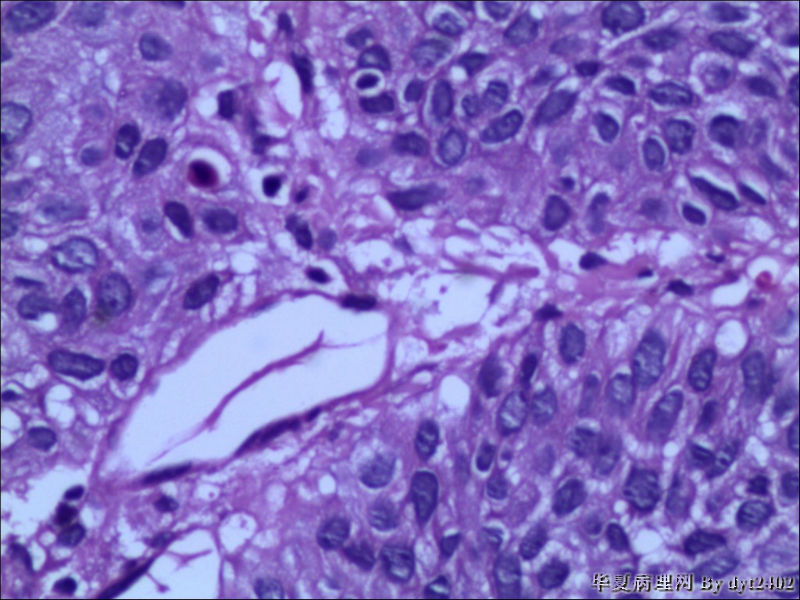

这样的外阴病变 发个原位癌是否合适?

• 这样的外阴病变 发个原位癌是否合适?图1

图1

原位癌够了,不排除其他地方有浸润。

似乎有浸润了

VIN III,做个银染或者标个免疫组化看一下基底膜是否完整。

看上去好像还完整 只是经常看见图5 那样结构的就觉得可能还有更重病变

VIN III